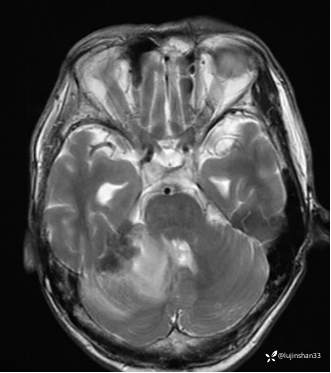

(2023-06-02 11:09,本院)磁共振(颅脑):1、右侧颞骨全切除术后改变,术区及相邻右侧斜坡、颞肌、咬肌、翼内外肌异常信号,考虑炎性肉芽肿性病变可能,请结合临床随诊复查;2、右侧小脑半球异常信号,考虑炎性病变可能;3、脑内散在缺血灶,软化灶形成;4、双侧蝶窦炎。

(2023-05-29 16:07,本院)CT颅脑:1、右侧颞骨全切除术后改变,术区见气体密度影,瘘管形成可能;术区多发软组织影,不完全除外炎性改变可能。2、左侧颞骨CT平扫未见明显异常。